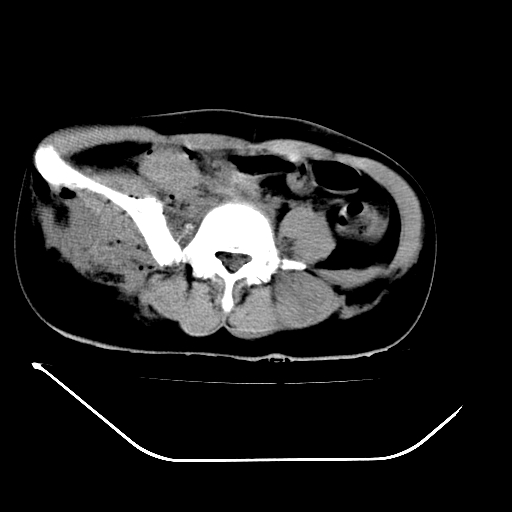

以下是引用liuyue在2008-7-19 13:02:00的发言:[br]1.肝右叶后下段及右肾挫裂伤伴腹腔积血。[br]2.右侧多发性肋骨骨折、横突骨折、右髂骨骨折伴周围软组织挫伤。[br]3.右侧腰大肌肿胀,并可见低密度影,如为气体,则肠道挫裂伤待除外。

以下是引用zhengfaming在2008-7-19 14:42:00的发言:[br]1.肝右叶后下段及右肾挫裂伤伴腹腔积血。脾脏挫裂伤待排[br]2.右侧多发性肋骨骨折、横突骨折、右髂骨骨折伴周围软组织挫伤。[br]3.右侧腰大肌肿胀,并可见低密度影,如为气体,则肠道挫裂伤待除外